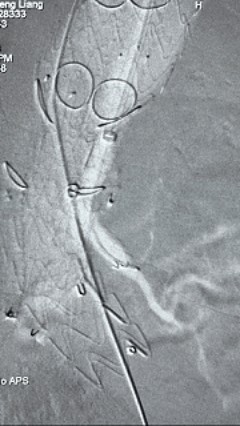

8. 从右侧股动脉入路送入腹主支架AB-24-12-110-S,近端重叠胸腹主动脉支架远端,调整好支架位置后释放。

9. 经左股动脉送入导丝导管,超选进腹主动脉支架短腿内,后沿导丝送入髂支,同理,右侧沿导丝送入髂支并释放,使用九州ku酷游顺应性球囊后扩各支架连接处及支架近远端,最后通过预留导管向瘤腔注入人纤维蛋白粘合剂数支,造影显示分支通畅。

术后评价

G-Branch在本例手术中展现出对扭曲解剖结构的出色适应性,针对该患者严重扭曲的瘤颈,支架系统的优异柔顺性使其能够顺利通过复杂路径,完成内脏分支血管的重建。